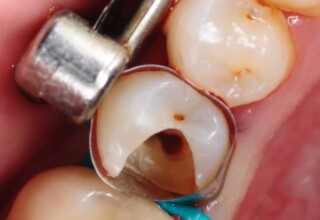

Posterior Tooth Root Canal Restoration with a Composite Resin Filling

The common restoration of a posterior tooth after a root canal is a crown. Its main purpose is to protect from fracture and concomitant extraction. In very few cases that specific criteria (mainly remaining tooth structure) are met or where finances predominate, an extensive composite filling can restore both aesthetics and function.

Restoration of a cracked molar with composite resin

Cracked teeth present a challenge in restorative dentistry both from the aspect of complexity of the restoration itself (usually large filings) and the necessary providings to avoid a complete fracture. The presented case demonstrates the simplest approach of a bonded direct restoration with composite resin. It is based on the principle of an adhesive filling that “holds” the remaining tooth structures “together”. The restored molar remained healthy for two years, then required a root canal and a crown was placed for maximum protection.